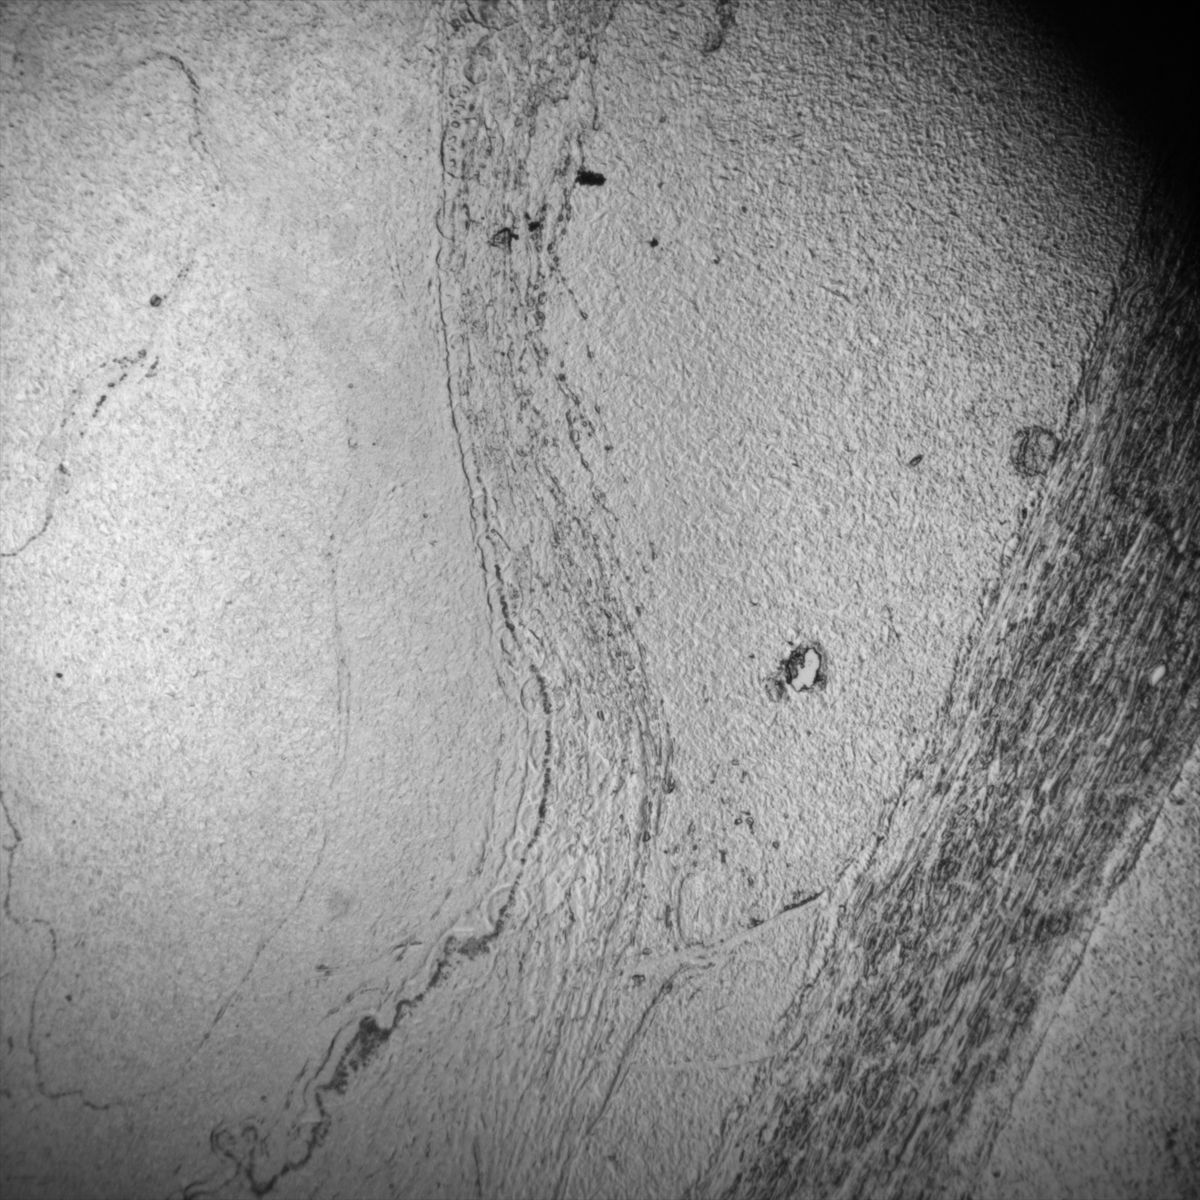

Healthy Eye

Overview 1

Overview 2

Overview 4